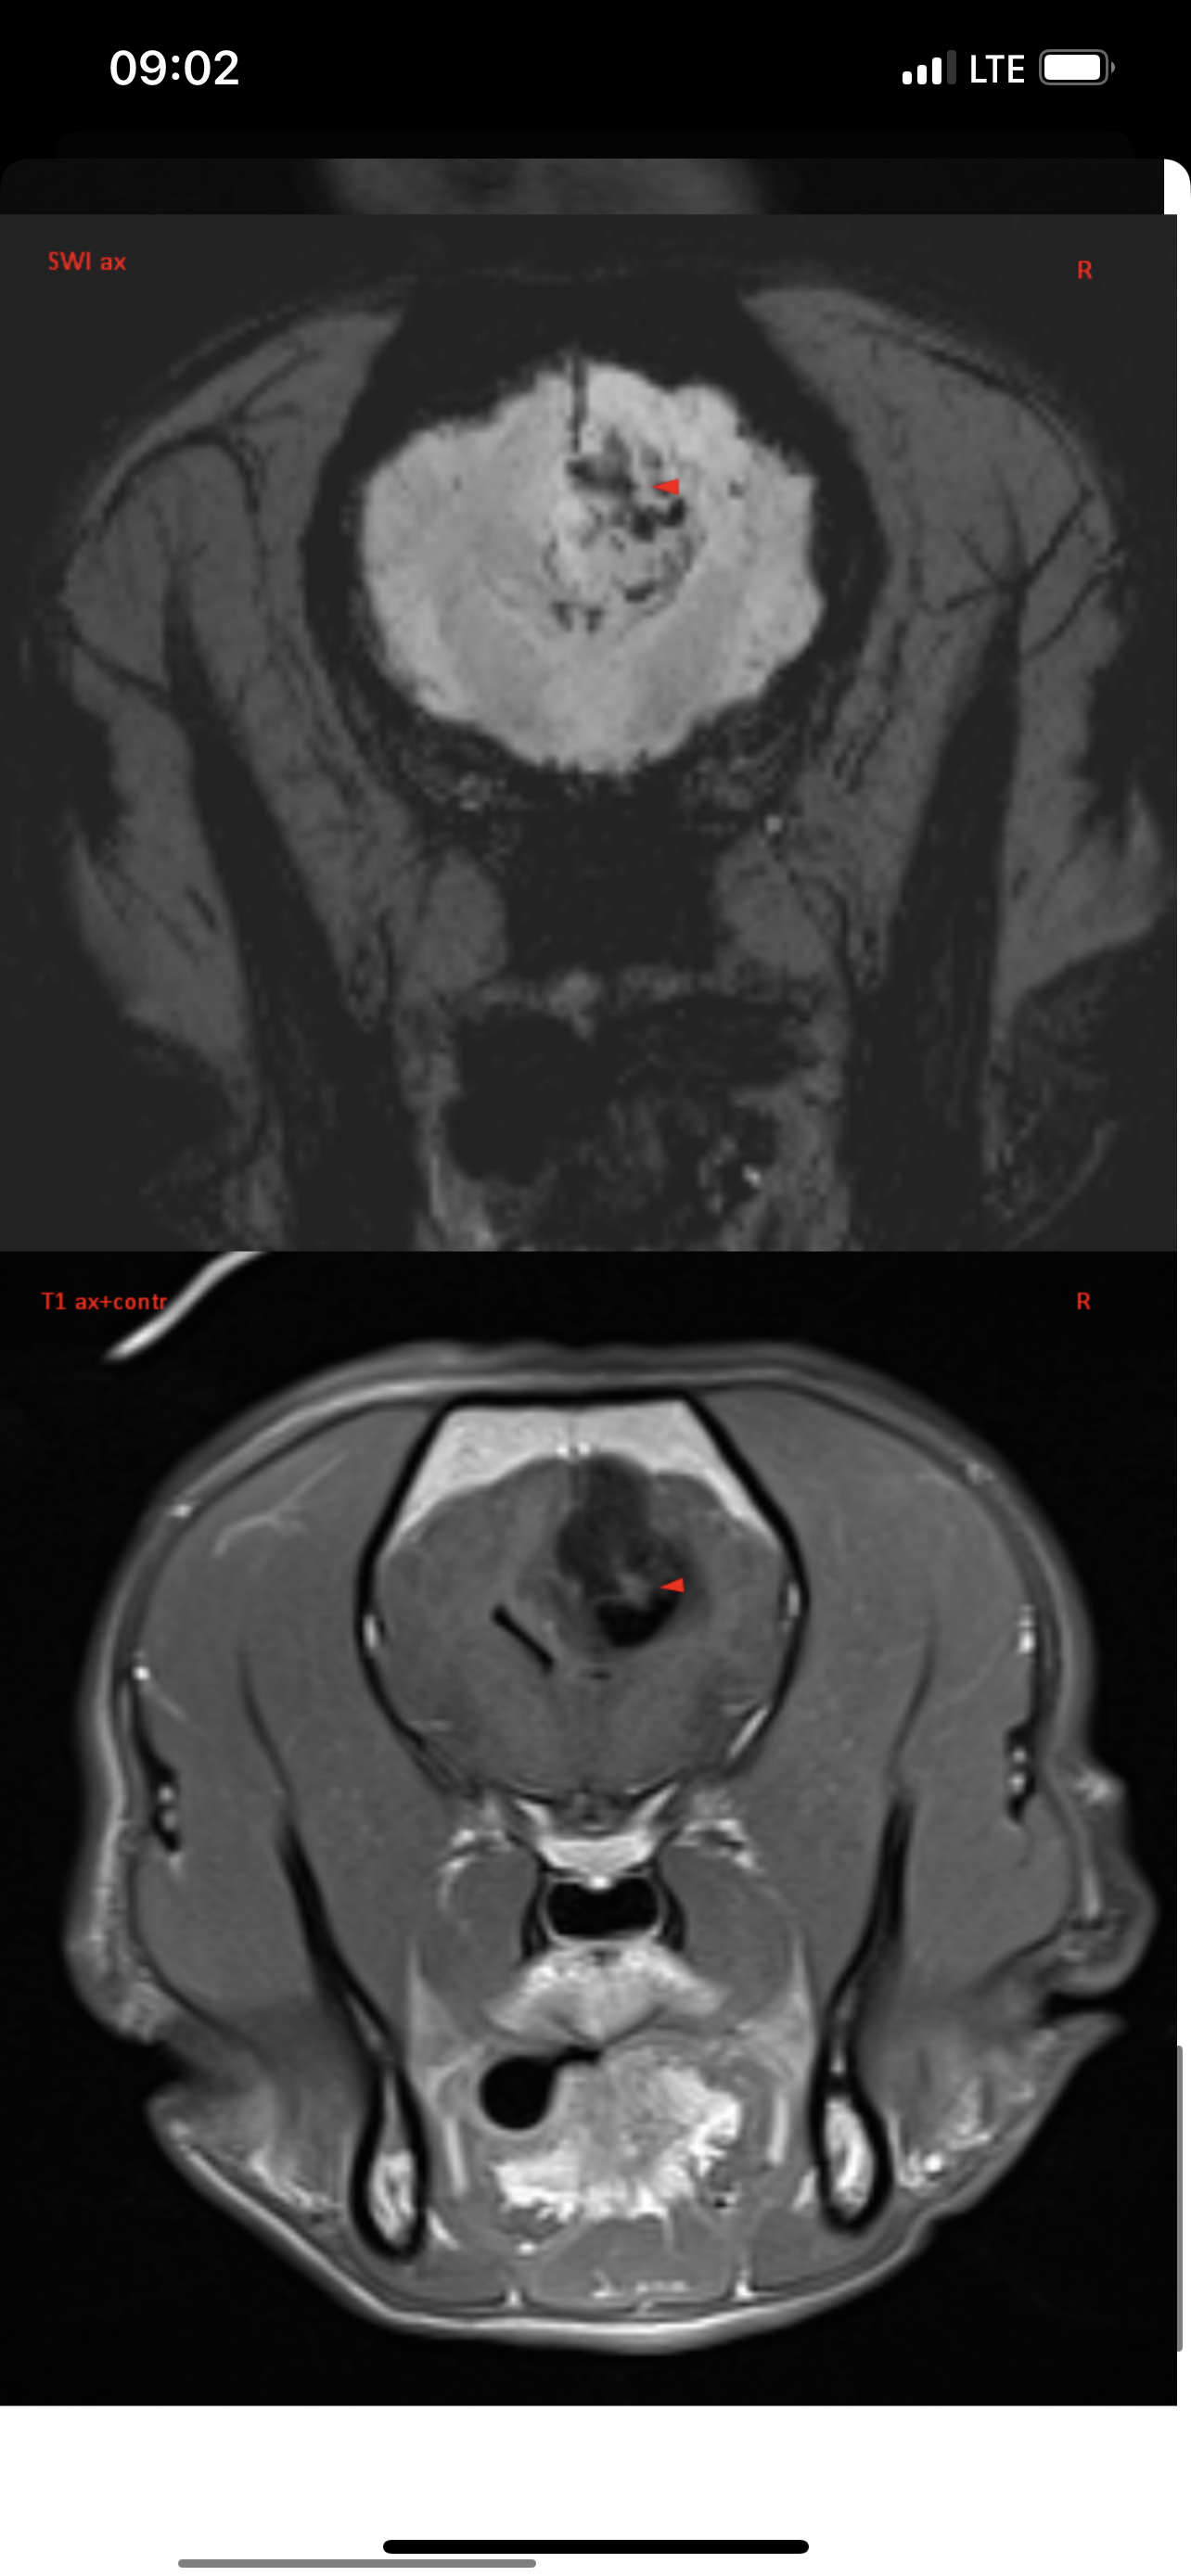

Вчера делали Марику МРТ в клинике Skolkovo Vet, если кому-то интересно, стоит чуть больше 12000₽. Результат неутешительный. Заключение:

МР-признаки новообразования в области лобной и теменной долей коры больших полушарий головного мозга справа, с очагами кровоизлияния и перифокальным отеком.

МР-признаки постсудорожных изменений.

Опухоль у моего мальчика(( она и вызывает судороги. Написала сегодня в вотс ап Хохлову, не знаю ответит ли, готова ехать к нему в клинику если он вообще принимает пациентов. К Дубовицкой попасть нереально, там очередь минимум на 1,5 месяца, есть онлайн консультация, стоит как и очный прием 7000₽, но ее рекомендуют скорее как второе мнение после очного осмотра у невролога. Рекомендовали еще Субботина из Белого Клыка, но увы, он по известным всем причинам с 2022 работает в вет клинике в Грузии. Продолжаю давать Кеппру и Габапентин

Итак, в прошлую субботу, когда въезд в Москву перегородили танки, над городом кружили вертолеты и не работала навигация, мы с Мариком были на приеме у уважаемого Алексея Валерьевича Хохлова. Он изучил снимки головного мозга, опухоль Марика он назвал скорее кистой и предположил, что живет он с ней уже давно, естественно ни о каком оперативном вмешательстве речи не идет. Спустя неделю после эпистатуса Марик почти полностью восстановился, но по лестнице сам еще не поднимается, Хохлов его состоянием доволен и никаких тревожных симптомов не обнаружил. Он прописал: Паглюферал1 - по 1/4 2 раза в день, Габапентин 300 по 1/2 2 раза в день, Кавинтон 5мг по 1/4 2 раза в день. Кеппру не прописал! Так же выдал рекомендации и список лекарств если будут приступы, что и как колоть, но эти схемы тут всем давно известны. Неделю мы принимаем все вышеизложенные препараты, пока все нормально, живем дальше с Божьей помощью!